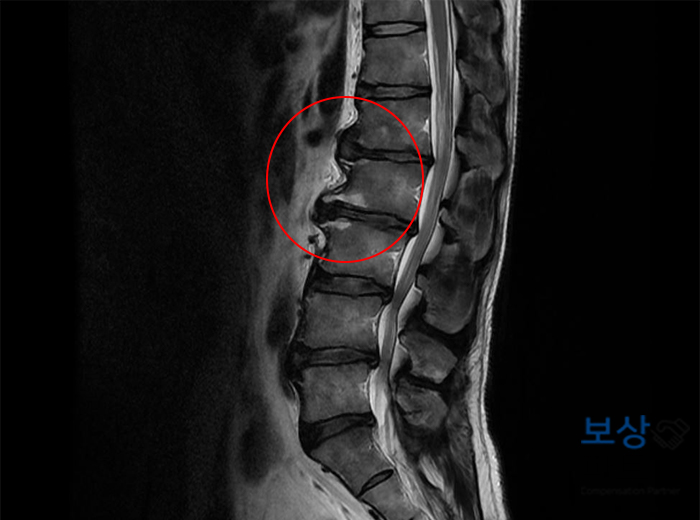

진단명 : 신경뿌리병증을 동반한 요추 및 기타 추간판장애 (M51.1) 병원 정밀 검사 결과, 신경뿌리병증을 동반한 요추(허리뼈)의 추간판장해 진단을 받으셨는데요. 흔히 허리 디스크라고 하는 증상이었습니다.

J 님의 경우, 돌출된 디스크가 신경을 누르는 증상이 심하여 수술적 치료가 불가피하였는데요. 관혈적 추간판 제거술을 시행한 후, 약 3개월간 안정을 취하게 되었습니다. 하지만 시간이 지나도 통증이 계속되는 증상이 남으셨는데요.